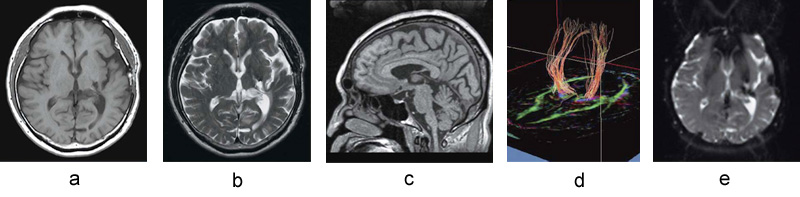

■脳卒中の後遺症に対するTMS治療前のfMRIの一例

脳の3D画像上の赤い部分は,Tapping(手指対立の開閉運動)による賦活領域を示す(aは左手,bは右手による運動。対象患者は右麻痺がある)。ただし,この賦活領域はTappingによって血流が増加した領域を示しており,神経活動の直接の評価ではない。

fMRIの撮像は,TMS治療前に,治療部位の同定目的に専用の8chヘッドコイルを用いて施行されている。撮像にあたっては,患者さんに左右の手指の開閉(Tapping)を,30秒ごとに30秒の休憩を挟みながら行ってもらい,その間の脳の血流変化をBOLD法で撮像し,fMRI解析ソフトウエア“SPM(Statistical Parametric Mapping)”を用いて賦活時と安静時の差分により解析する。これに加えてMRIでは,T1強調像,T2強調像,3D-T1強調像,拡散テンソルトラクトグラフィを撮像し,総合評価によって治療部位が同定される。BOLD法の撮像は6分で行われるが,患者さんへの事前説明や動作練習なども行うため,すべての撮像を終えるのに約1時間かかるという。